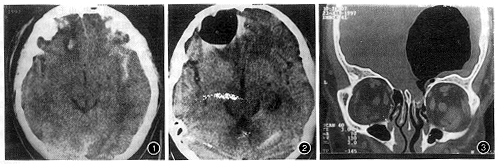

患者 男 患者 男,26岁。车祸后右眼视物不见1个月,伴头痛入院。体检:右眼视神经萎缩。直接光反射消失,间接光反射存在。于外伤当日CT平扫示:右侧额骨骨折,右侧额叶脑挫裂伤,外侧裂出血,但未见颅内积气(图1)。给以间断鼻腔吸氧,10日后头颅CT示:右侧额部气囊肿形成,大小约2.0 cm×2.0 cm×3.0 cm(图2)。右侧筛窦骨壁不规则骨折线,右侧视神经管内侧骨壁骨折。1个月后头颅CT示:右侧额部气囊肿增大为5.5 cm×5.5 cm×6.0 cm,与右侧筛窦相通(图3)。CT诊断:右侧额部硬膜下气囊肿。右侧筛窦骨壁骨折,右侧视神经管内侧壁骨折,右侧额骨骨折。行右侧额骨钻孔颅内积气引流术,术后气囊体积明显减小。经鼻腔填塞油纱条和明胶海绵,气囊逐渐减小至消失。

图1 外伤当日CT平扫:双侧额叶不均匀混杂密度,可见灶性高密度影,左侧外侧裂内亦见高密度影充盈。考虑脑组织挫裂伤,未见颅内积气征象 图2 外伤10日后CT示:右侧额部有一2.0 cm×2.0 cm×3.0 cm的气囊肿,未见头皮下软组织内积气及与外界交通 图3 外伤后1个月高分辨率CT冠状扫描:清晰显示筛窦骨壁骨折。右侧额部气囊增大为5.5 cm×5.5 cm×6.0 cm,与右侧筛窦连通